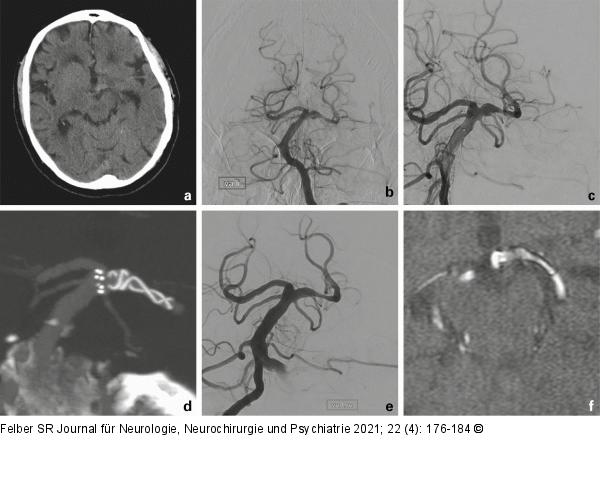

Abbildung 4a-f: Arteriosklerotisches Aneurysma Der 82-jährige Patient kam mit Kopfschmerzen zur Aufnahme. Im CT zeigte sich eine kleine Hyperdensität an der Basilarisspitze nach links (a). Eine Lumbalpunktion erbrachte xanthochromen Liquor. Die Angiographie zeigte eine dolichoektatische Erweiterung der linken A. vertebralis und der A. basilaris mit einem fusiformen Aneurysma des linken P1-Segmentes (b). Es wurde ein flusskorrigierender Stent implantiert (c, d). In der Jahreskontrolle (e) ist das Aneurysma rückgebildet und die MR-Angiographie 5 Jahre nach der Behandlung (f) ergibt keinen Anhaltspunkt für ein Rezidivaneurysma. Auch die dolichoektatische A. basilaris zeigte einen stabilen Verlauf. |

Abbildung 4a-f: Arteriosklerotisches Aneurysma